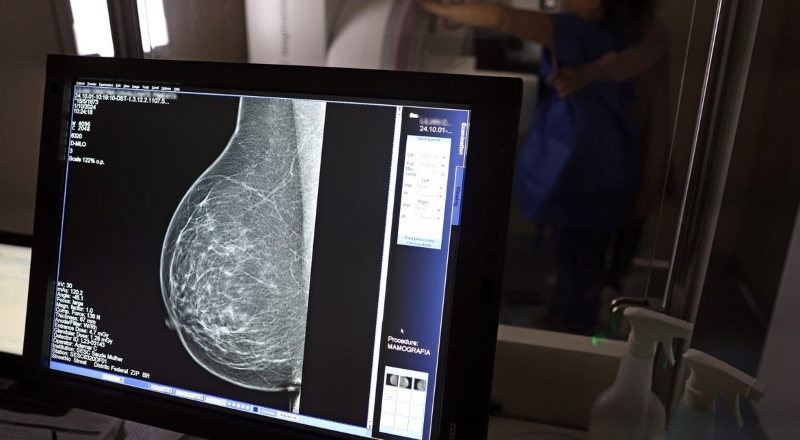

Outubro Rosa: mulheres do Norte ainda têm o menor acesso à mamografia, revela relatório de 2025

Brasil – No mês de conscientização sobre o câncer de mama, um relatório destaca a importância de acesso igualitário ao rastreamento e tratamento da doença. Segundo o Atlas da Radiologia no Brasil, do Colégio Brasileiro de Radiologia e Diagnóstico por Imagem (CBR), o acesso aos mamógrafos ainda é um desafio.

O país tem 6.826 equipamentos registrados, sendo 96% em funcionamento. Metade deles está disponível no Sistema Único de Saúde (SUS), responsável por atender 75% da população. Isso equivale a 2,13 mamógrafos por 100 mil habitantes dependentes do SUS.

Na saúde suplementar, que cobre 25% da população, o cenário é mais favorável: 6,54 aparelhos por 100 mil beneficiárias, quase o triplo da rede pública. O Acre exemplifica essa disparidade — são 35,38 mamógrafos por 100 mil habitantes na rede privada, contra 0,84 no SUS.

Há disparidades regionais. Roraima tem a menor proporção (1,53 por 100 mil), seguida do Ceará (2,23) e Pará (2,25). A Paraíba lidera o ranking (4,32), à frente do Distrito Federal (4,26) e do Rio de Janeiro (3,93).

O Brasil tem uma cobertura muito baixa de mamografias: 24%. O ideal recomendado pela Organização Mundial da Saúde é de 70%. Mesmo em lugares como o estado de São Paulo, que tem a maior concentração de mamógrafos do país, a taxa gira em torno de 26%.

Em setembro, o Ministério da Saúde ampliou as diretrizes de rastreamento, recomendando que mulheres entre 40 e 49 anos realizem mamografias, mesmo sem sintomas. De acordo com o Instituto Nacional do Câncer (Imca), mais de 73 mil mulheres recebem o diagnóstico de câncer de mama anualmente no Brasil.